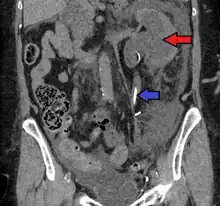

- Stone causing hydronephrosis[16]

- Urine jets[16]